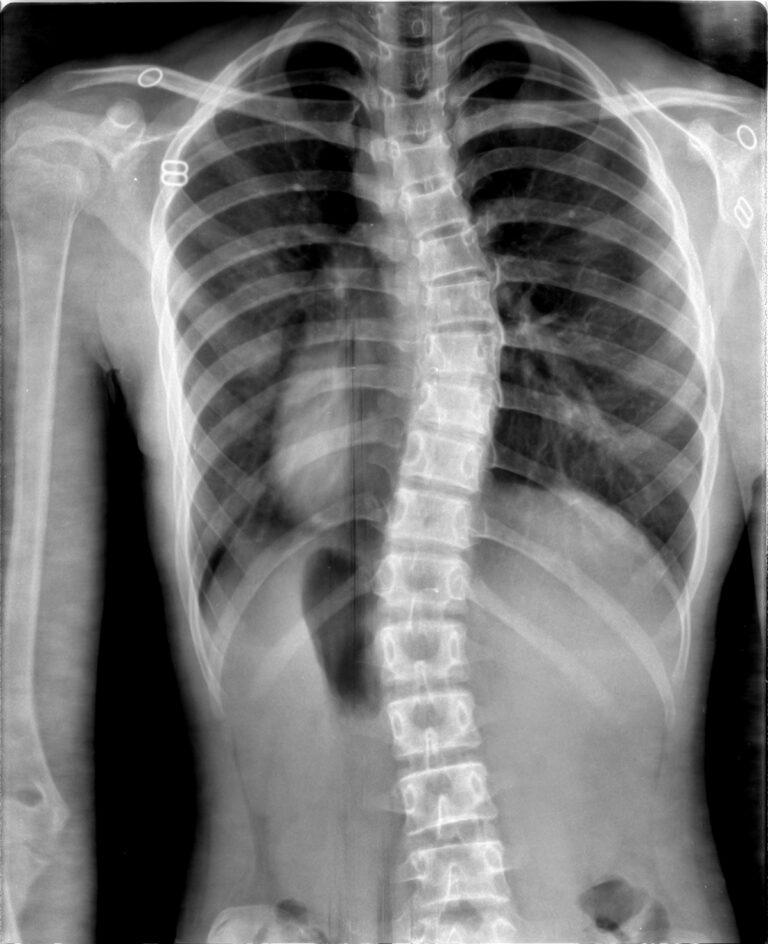

Mild scoliosis is typically classified based on Cobb angle measurements, which determine the extent of the spinal curvature. A Cobb angle between 10 and 25 degrees is generally considered as mild scoliosis. This measurement is obtained through specialized imaging techniques, such as X-rays, which allow healthcare professionals to accurately assess the curvature and its severity.

- Uneven shoulder height: One shoulder appearing higher than the other or a shoulder blade protruding more prominently on one side.

- Uneven waistline: Noticeable asymmetry or an apparent shift of the waistline when viewed from the back.

- Head and neck misalignment: The head might appear slightly off-center, not aligning directly above the pelvis.